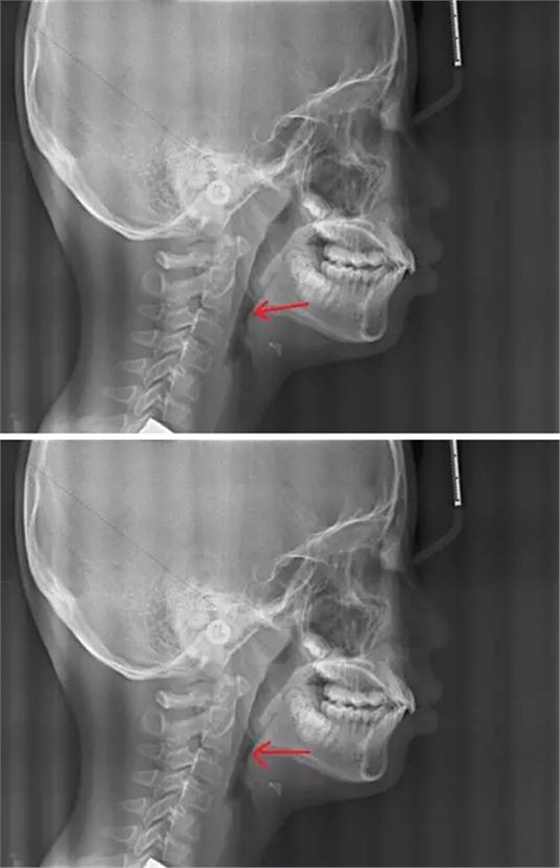

我們再來看兩張肥大的扁桃體